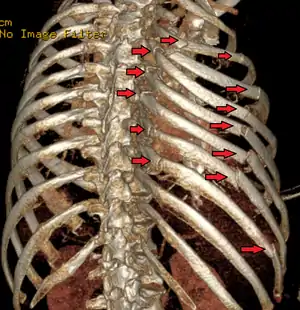

| A 3D reconstruction from a CT scan showing a flail chest. Arrows mark the rib fractures. | |